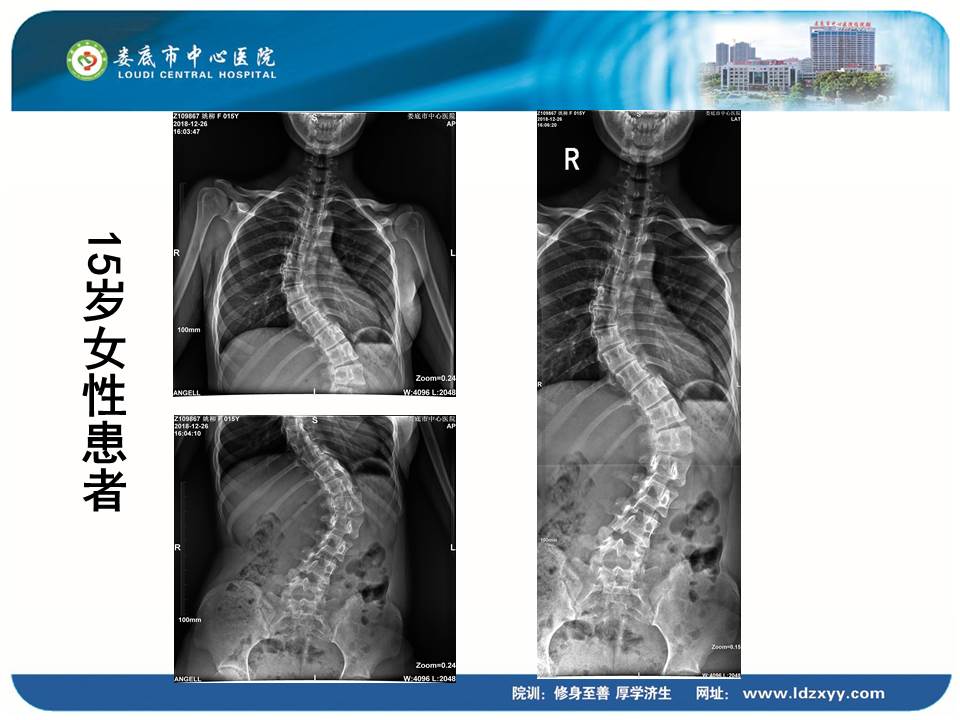

湖南影像學委員、婁底市放射學會副主任委員、婁底市中心醫院放射科劉海潮副主任,則結合動態DR設備的全身拼接應用,分享了動態DR在骨科中的多項應用價值。劉海潮主任認為:由于常規DR的技術限制,長期以來放射科應用傳統拍片并不能有效解決重疊部位的清晰顯影,容易造成漏診誤診,并且受制于成像視野的大小,不能有效顯示脊柱四肢全長的整體結構及病變。而動態DR的17*17英寸大視野成像,配合900多萬的高清像素及可視化的操作,較好地彌補了傳統拍片的不足,而且初步實現了普放向精準診斷方向的轉變。劉主任分享了動態DR在全脊柱攝影、全脊柱拼接、脊柱畸形,全下肢X線攝影、全下肢拼接、關節置換中的多項應用,通過站立負重位,快速、便捷攝取 2~3 張原始圖像。在相鄰兩幅原始圖像的重疊部分,對重疊圖像的特征點迅速匹配,進行智能無縫融合處理,將數張有重疊部分的圖像拼成一幅大型的無縫高分辨率圖像。劉海潮主任評價:動態DR通過強大的圖像后處理技術,比如邊緣增強、灰階處理,以及對對比度和銳利度的可調節性,大大提高了拼接影像的質量。

▲全身拼接應用示例